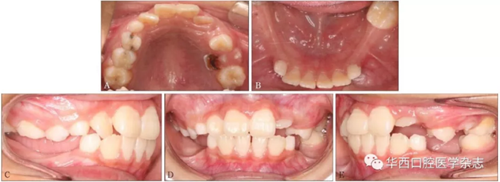

患者,男,10歲,2016年7月因右后牙未萌求治。無正畸治療史、拔牙史、全身系統(tǒng)疾病史,家族成員中無類似畸形?;颊咧委熐翱趦?nèi)像見圖1。

A:上頜面像;B:下頜面像;C:右側像;D:正面像;E:左側像。

圖 1 治療前口內(nèi)像

臨床檢查:混合牙列,左側磨牙中性關系,前牙淺覆、淺覆蓋,右側側切牙反,下頜恒切牙及左下頜第一磨牙正常萌出,雙側下頜乳尖牙尚未脫落,下頜其余牙齒未見,黏膜色澤正常(圖1)。